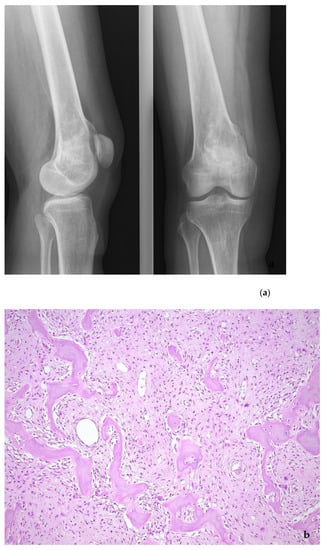

Figure 11.

Parosteal osteosarcoma, typically presenting as a mineralized mass at the back of the distal femur, X-ray (a), and whole mount section (b). At high power, the tumor consists of parallel bone trabeculae and a typical spindle cell proliferation (c). MDM2 expression is present as well (d).

Figure 12.

Low-grade central osteosarcoma, showing a lytic lesion the distal femur on X-ray (a). On histology, the tumor strongly mimics fibrous dysplasia, with the very irregular bone trabeculae embedded in e fibrous stroma (b). The amplification of the MDM2 gene supports the diagnosis (c).

Low-grade osteosarcomas are rare and are subdivided in parosteal and low-grade central osteosarcoma. In both tumors, the diagnosis is often impossible in the absence of imaging features, because they often look deceptively bland. Parosteal osteosarcoma represents 4–5% of all osteosarcomas and is the most frequent surface osteosarcoma. It typically develops on the posterior surface of the distal femur of young adults, mainly in the third decade. The humerus can also be rarely involved. On imaging, a heavily mineralized mass attached to the cortex is seen (Figure 11). Histologically, fascicles of non-atypical spindle cells admixed with parallel bone trabecula are typical (Figure 11). In half of the cases, cartilage islands can be seen, and about half of the tumors transgress the cortex and invade the medullary cavity. Fifteen to 43% dedifferentiate into a high grade (osteo)sarcoma []. Low grade central osteosarcoma only accounts for 1–2% of osteosarcomas and is mainly seen in the metaphysis of long bones, tibia and femur being most affected. This tumor rarely involves jaw bones, axial and small tubular bones. Half of the cases occur in the second to third decade. On imaging, a large lytic to mineralized mass is seen, often associated with focal cortical disruption, which can be hard to see (Figure 12). On histology, the tumor consists of a fascicular and moderately cellular fibroblastic proliferation, with minimal or no atypia. The neoplastic bone can present as curved bone trabeculae, mimicking fibrous dysplasia, or as longitudinal seams of bone, as seen in parosteal osteosarcoma (Figure 12). Bone formation can even be absent, resulting in a picture that resembles desmoplastic fibroma or low-grade fibrosarcoma. Very rarely dedifferentiation can occur resulting in a classical high-grade osteosarcoma-like picture []. Both tumors harbor long marker or ring chromosomes with amplified 12q13-15 regions, including the MDM2 and CDK4 genes [,]. In a high proportion of cases, immunohistochemical MDM2 and/or CDK4 expression can be found as well. In this respect, search for MDM2 amplification/expression can be very useful to distinguish these low-grade sarcomas from their—often benign—mimics (Figure 11 and Figure 12) []. The prognosis of both neoplasms is excellent, with 5-year survival rates of 90% upon complete resection. Chemotherapy is only administered in cases of dedifferentiation, when the prognosis is that of a conventional osteosarcoma. Interestingly, when low-grade central or parosteal osteosarcoma dedifferentiate into a high-grade sarcoma, they retain their MDM2/CDK4 amplification and overexpression. In addition, the finding of MDM2 and/or CDK4 amplification/overexpression in a high-grade osteosarcoma indicates progression/dedifferentiation from a low-grade osteosarcoma and practically excludes a primary conventional high-grade osteosarcoma [].